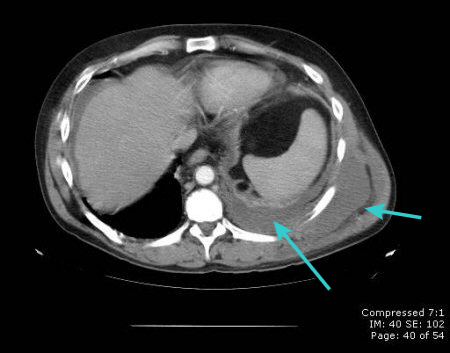

CT scan showing loculated pleural effusion

From the collection of Dr Ami Rubinowitz; used with permission